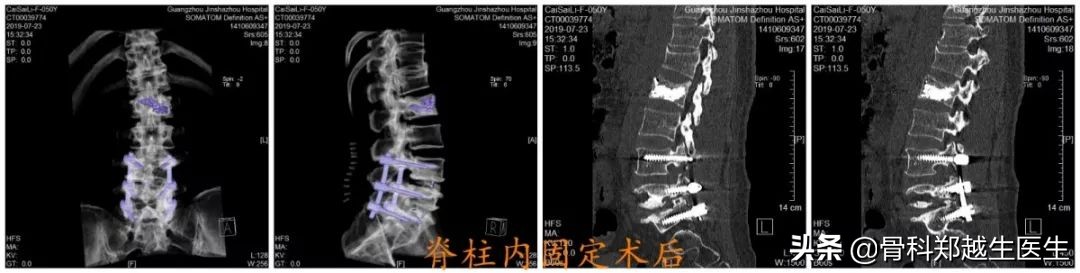

患者诊断明确后,在我科行三期手术治疗,第一期,行腰椎经皮椎体成形术,术后腰部疼痛缓解,可坐起、站立行走。第二期,颈椎后路椎管内肿瘤摘除术,术后四肢麻木明显改善,肢体活动功能改善。第三期,腰椎后路椎间植骨融合椎弓根钉内固定术,术后患者可长时间站立、行走,生活基本恢复正常。